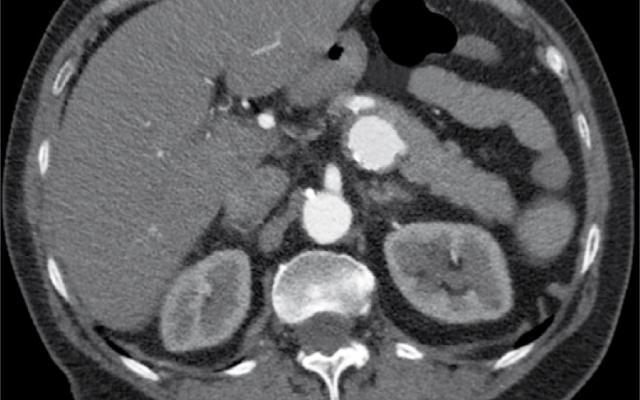

Een 73-jarige vrouw met hypertensie presenteerde zich op de Spoedeisende Hulp met acuut ontstane, hevige buikpijn die continu sinds 10 h aanwezig was. Daarnaast was zij misselijk en had zij gebraakt. Bij lichamelijk onderzoek zagen wij een zieke vrouw met pijn, maar zonder koorts. Patiënte was hemodynamisch stabiel. Peri-umbilicaal gaf zij percussie- en loslaatpijn aan. Laboratoriumonderzoek toonde geen afwijkingen. De klinische symptomen pasten bij een acute buik. Differentiaaldiagnostisch dachten wij aan coprostase, mogelijk op basis van een ruimte-innemend proces, of ischemie van het mesenterium. Op röntgenopnamen van de thorax en van het abdomen werd rechtszijdige coprostase gezien, zonder een…